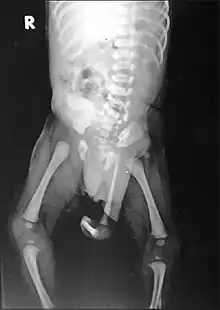

| Radiograph of a human child with polymelia | |